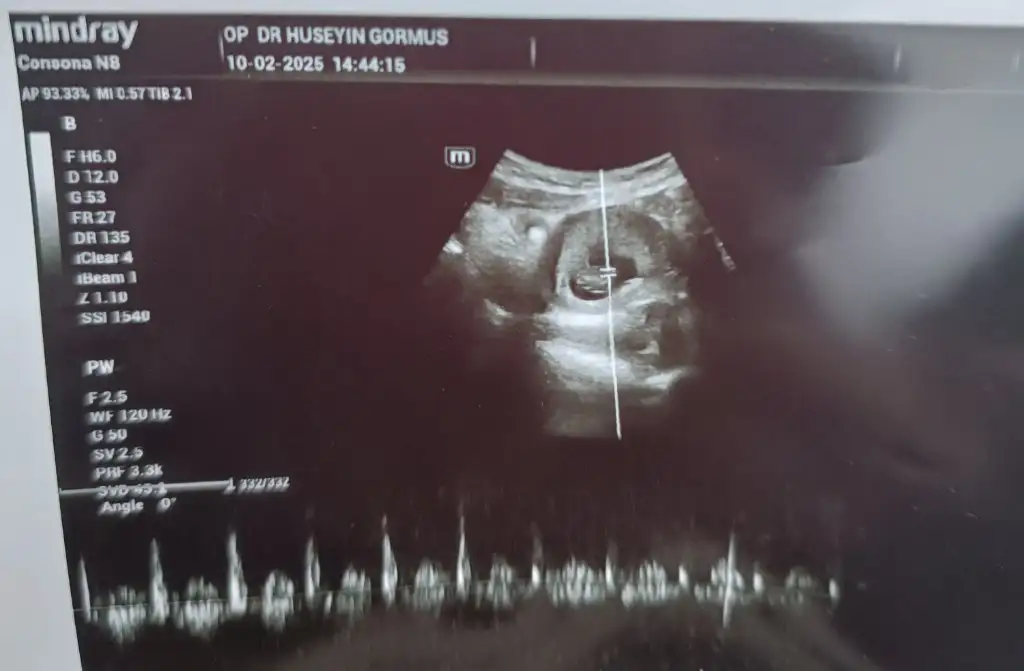

C cimcimekizimm konu sahibi sensin herhalde banada tahminde bulunurmusun lütfen 8 haftalık karından usg

Eklentiler

• IMG_20250210_140753.webp

19,2 KB · Görüntüleme: 43

Ben biliyorum cinsiyetini ama meraktan benimkisi işe yarıyor mu sahi